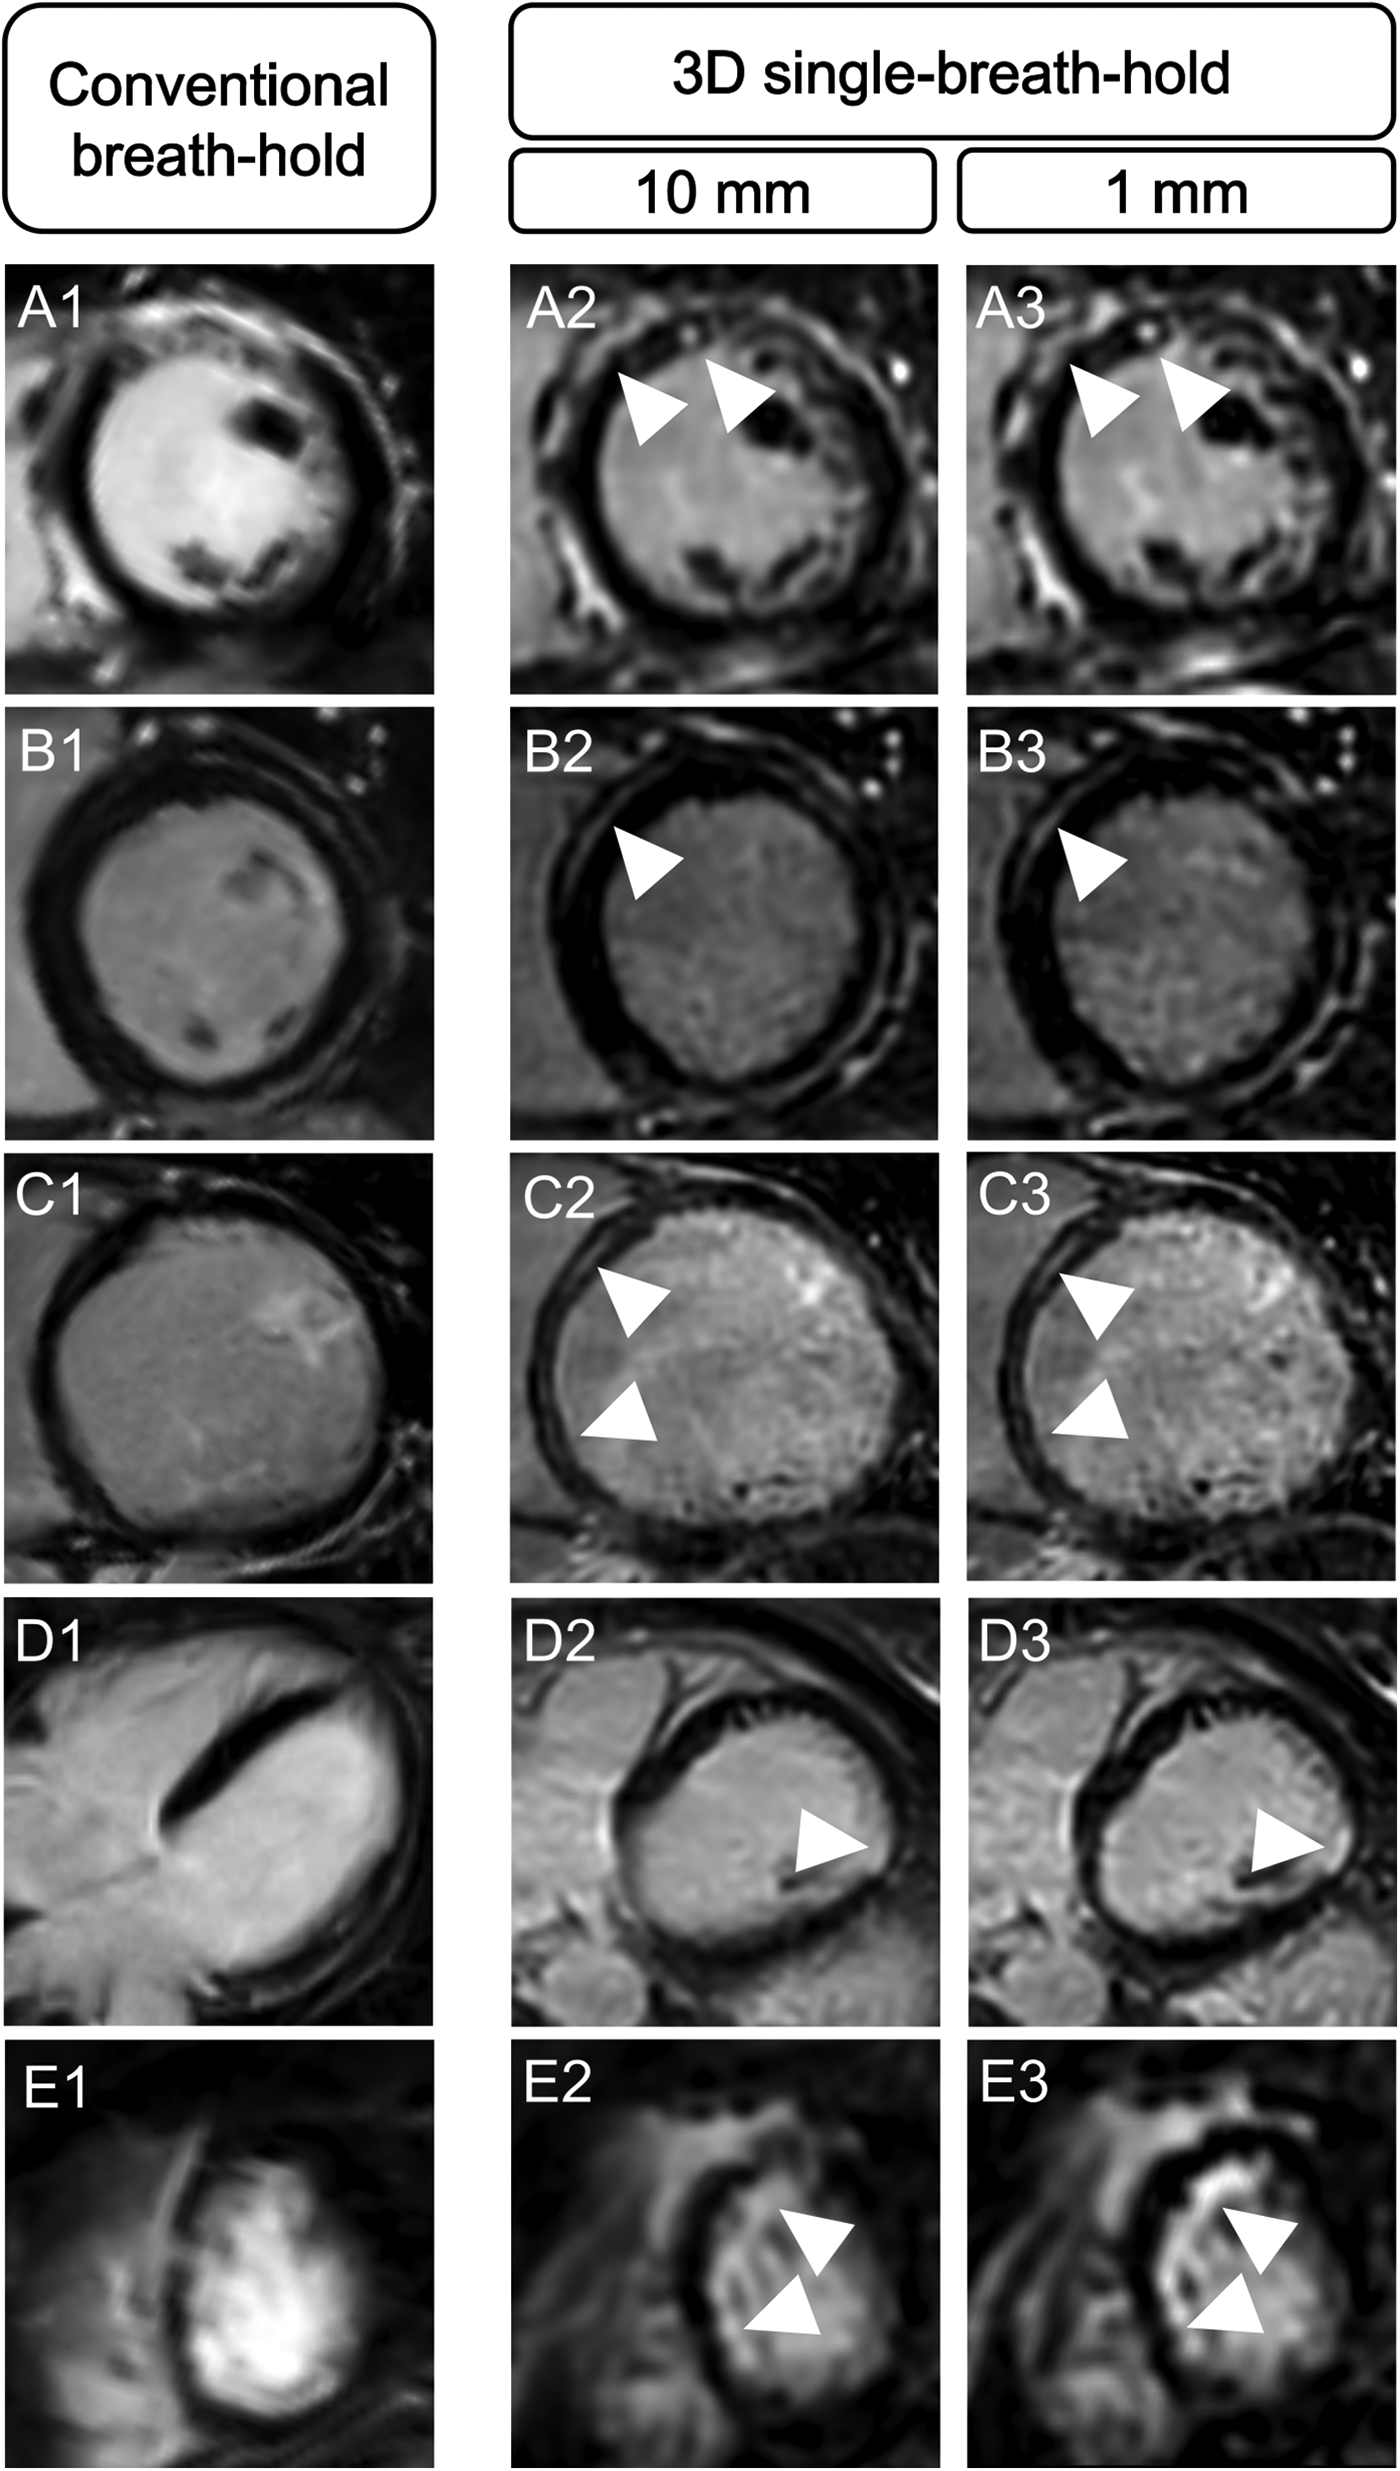

Averaged for both readers, depiction of transmural lesions was comparable between both techniques (3D single-breath-hold-LGE: 55.5, conventional breath-hold LGE: 54.5). In 3D single-breath-hold-LGE readers identified more lesions in subendocardial (43 vs. 35.5), mid-myocardial (52 vs. 42), and subepicardial localization (95.5 vs. 84). Additionally, readers were able to detect a higher number of small LGE lesions, as defined by a transmural extent <50%, using 3D single-breath-hold-LGE than with conventional breath-hold LGE (1%–25%: 60.5 vs. 47.5, 26%–50%: 79.5 vs. 67.5). Delineation of lesions with a larger transmural extent (>50%) was comparable between both techniques (3D single-breath-hold-LGE: 49.5, conventional breath-hold LGE: 46 for 51%–75%; 3D single-breath-hold-LGE: 56.5, conventional breath-hold LGE: 55 for 76%–100%). Figure 3 shows exemplary additional findings in 3D single-breath-hold-LGE in ischemic and non-ischemic cardiomyopathies.

Figure 3

Illustration of the higher spatial resolution of 3D isotropic single-breath-hold LGE with additional LGE findings. Comparison of conventional breath-hold LGE and 3D isotropic single-breath-hold LGE reconstructions demonstrating additional LGE findings in 3D isotropic single-breath-hold LGE in patients with sarcoidosis (A1–A3, arrowheads), myocarditis (B1–B3, arrowheads), dilated cardiomyopathy (C1–C3, arrowheads), myocardial infarction with non-obstructive coronary arteries (D1–D3, arrowhead), and anterior wall infarction (E1–E3, arrowheads).